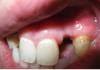

Заринка Опубликовано 12 октября, 2013 Поделиться Опубликовано 12 октября, 2013 (изменено) Мне 29 лет и у меня было 2 молочных боковых резца на верхней челюсти. Сохраняла как могла, но увы... один сломался. Проконсультировавшись с доктором, было принято решение сделать синус-лифтинг, т.к. кость атрофировалась и установить 2 импланта. В мае была проведена операция. По прошествии 4-х месяцев был сделан снимок, который показал, что на левой стороне кость сформировалась не так как нужно, но возможность установки есть, просто имплант будет поставлен чуть выше второго (со слов доктора) и 24.09.2013г. мне установили импланты. С этой стороны уже сейчас видно как ушла десна, смотрится очень не красиво. Можно ли это как то исправить? и на каком этапе?Заранее спасибо. Изменено 12 октября, 2013 пользователем Заринка Ссылка на комментарий

Заринка Опубликовано 14 октября, 2013 Автор Поделиться Опубликовано 14 октября, 2013 Дак все таки можно что-то с десной сделать или у меня "железо" торчать будет "над зубом"?Снимки не получилось пока взять Ссылка на комментарий

Bier Опубликовано 15 октября, 2013 Поделиться Опубликовано 15 октября, 2013 Сфотографируйте как выглядит это сейчас Ссылка на комментарий

Заринка Опубликовано 16 октября, 2013 Автор Поделиться Опубликовано 16 октября, 2013 Ссылка на комментарий